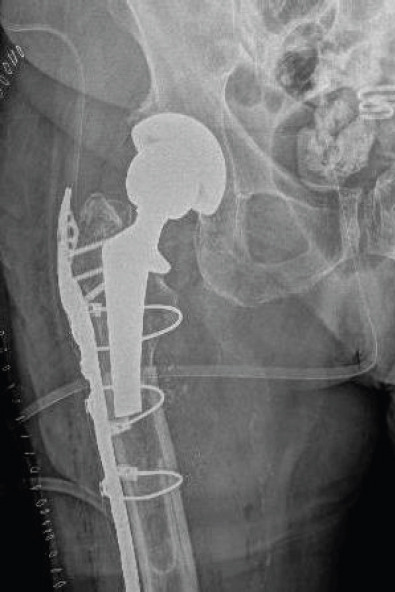

Case report: An 88-year-old female with multiple comorbidities, including osteoporosis and a history of bisphosphonate therapy, presented with an APFF of the right femur following a ground-level fall. One year prior, she had undergone uncomplicated THA with a long cylindrical, fully porous-coated femoral stem. Radiographs revealed a transverse fracture at the subtrochanteric region, lateral cortical thickening, and femoral stem breakage. Given the patient's medical history and the complexity of the fracture, revision surgery was indicated. Surgical intervention included the preservation of the proximal femoral stem and the removal of the distal stem segment, combined with periprosthetic plate fixation and cortical strut allograft for stabilization.